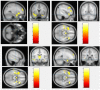

Methods: In this study, we recruited 72 patients with schizophrenia and 74 healthy individuals matched by age and sex to investigate the structural brain changes that may serve as prognostic biomarkers, indicating evidence of neural dysfunction underlying schizophrenia and subsequent cognitive and behavioral deficits. We used voxel-based morphometry (VBM) to determine these changes in the three tissue structures: the gray matter (GM), white matter (WM), and cerebrospinal fluid (CSF). For both image processing and statistical analysis, we used statistical parametric mapping (SPM).

Results: Our results show that patients with schizophrenia exhibited a significant volume reduction in both GM and WM. In particular, GM volume reductions were more evident in the frontal, temporal, limbic, and parietal lobe, similarly the WM volume reductions were predominantly in the frontal, temporal, and limbic lobe. In addition, patients with schizophrenia demonstrated a significant increase in the CSF volume in the left third and lateral ventricle regions.